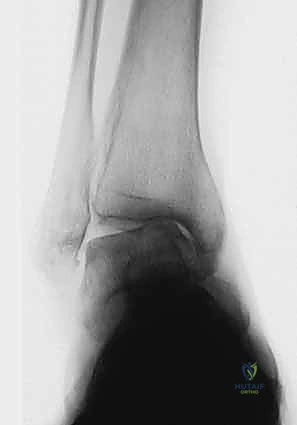

2. التصوير بالأشعة السينية بوضعية الوقوف (Weight-bearing X-rays)

هذا هو حجر الأساس في التشخيص. الأشعة العادية والمريض مستلقٍ لا تظهر الحجم الحقيقي للتشوه. يطلب الدكتور هطيف صوراً خاصة والمريض يحمل وزنه كاملاً على قدميه.

* المنظر الأمامي الخلفي (AP View): لتقييم المسافة المفصلية وتحديد زاوية سطح الساق (Tibial Anterior Surface Angle - TAS).

* منظر سالتزمان (Saltzman View): وهو منظر إشعاعي متخصص جداً لتقييم محاذاة الكعب الخلفي بالنسبة لمحور الساق، وهو أمر حاسم في التخطيط الجراحي.